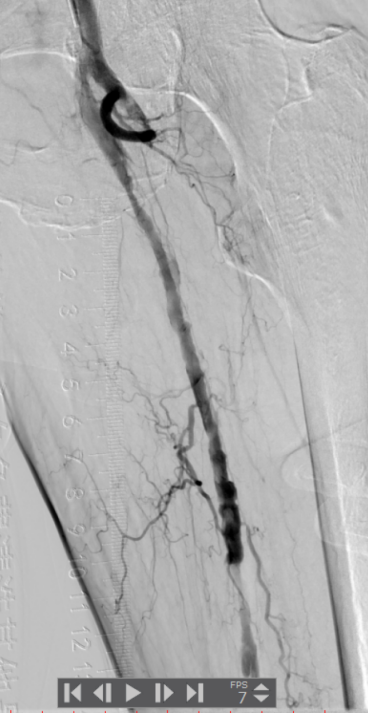

血管外科姜坤主任团队仔细分析患者病情,该患者在动脉硬化闭塞基础上继发血栓形成,且血栓负荷量大,身体状况差,行麻醉及开放手术取栓的风险大,遂制定了微创腔内的手术方案,采用动脉机械血栓清除+血管成形术。

术中选用Rotarex导管行血栓清除,对管腔内残留的血栓放置溶栓导管,最后采用球囊扩张狭窄病变,管腔获得满意。